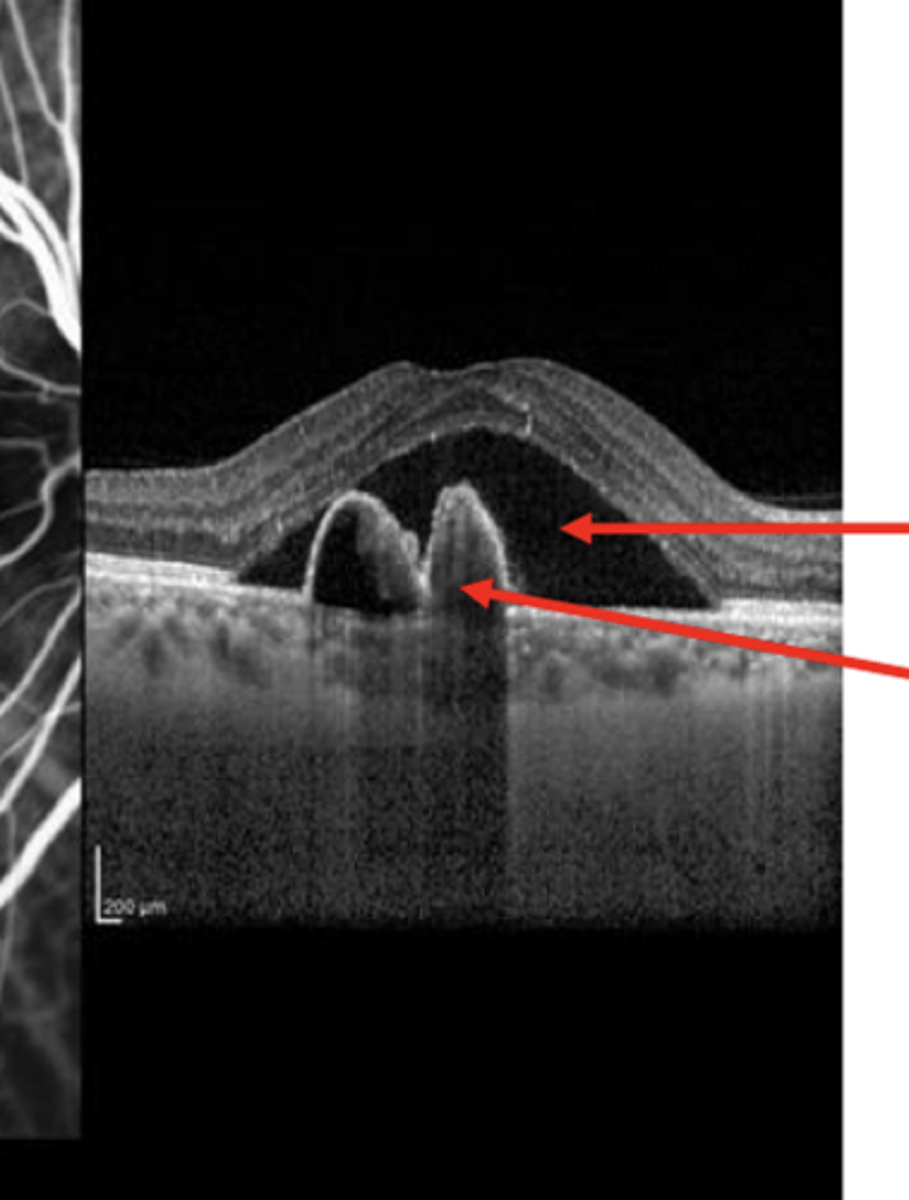

Polypoidal Choroidal Vasculopathy/Aneurysmal Type 1 Neovascularization (PCV/AT1)

Aneurysms of the choroidal vessels

What are these bright bulbs on OCT-1?

-Serous Detachment

-RPE Detachment

-In the presence of choroidal aneurysms in the same place

What is present in this pic?